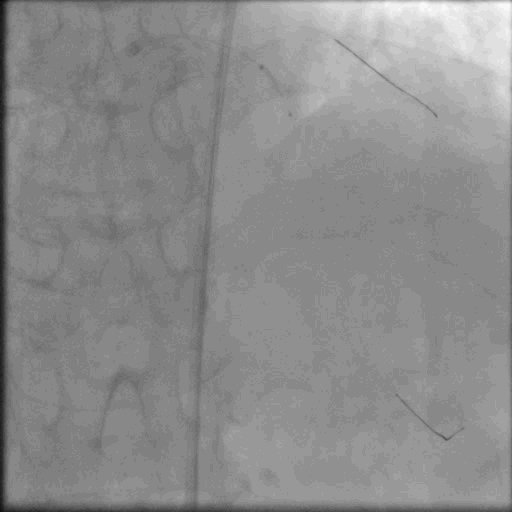

SION导丝送入D1远端,Sprinter1.5*15球囊扩张D1近端以显示LAD闭塞部位

D1扩张后造影显示LAD闭塞开口位于D1发出处,微导管Corsair支持下Filder XTR未能通过病变